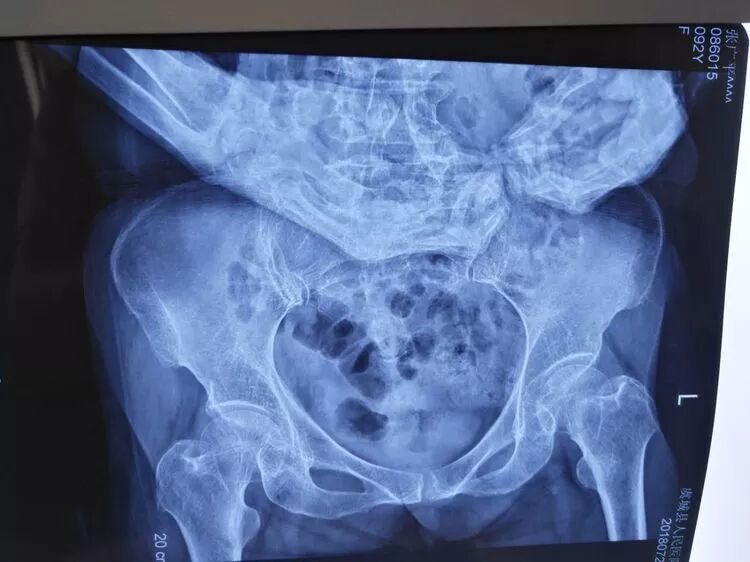

术前X线片